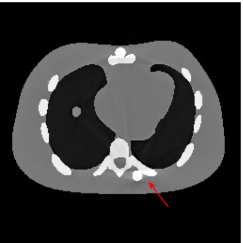

Figure 7(a) shows that the reconstructed NCAT phantom from FBP has severe metal artifacts and is noisy. The reconstructed image from the unweighted JSR model (3.2) shown in Figure 7(b) has a better visual effect with noticeably less noise and metal artifacts. Sharp edges are also well preserved except for the blurry effects in the region surrounding the metals. The reconstructed image from NMAR shown in Figure 7(c) also has most of the metal artifacts suppressed and the regions surrounding the metals are much less blurry than the unweighted JSR. However, the unweighted JSR does a better job than NMAR in suppressing noise and preserving sharp image features away from the metals. TV-FADM is able to reconstruct images with minimum metal artifacts and noise, as shown in Figure 7(d). However, the metal components are fused with nearby structures which is highlighted by the red arrow. The reconstructed image from proposed re-weighted JSR model has the best overall quality with rather minor metal artifacts.

Figure 8 shows the reconstructed cerebral phantom from different methods. We highlight some regions with more distinct differences with red contours. Since the cerebral phantom contains more textures, it is more challenging than the NCAT phantom. The pros and cons of these methods are mostly the same as the previous example. However, we note that the reconstructed image from TV-FADM shown in Figure 8(e) has severe artifact, which is due to the well-known staircase artifact of TV regularization. We found that TV-FADM is relatively sensitive to the choice of its parameters. It is not easy to balance between sharpness of image features and metal artifacts reduction. The soft tissue around metal components is also not well preserved by the NMAR method as indicated by the blue arrow in Figure 8(d). Furthermore, the circled areas in Figure 8(d) show that there are still some artifacts around the metal. Same as the NCAT phantom, the proposed re-weighted JSR model has the best overall performance. Notice that the intensity of metals in Figure 8(d) and 8(f) seems lower than the rest of the reconstructed images. This is because we set the intensity of the metal components in the segmentation with the same mean value as that of bones. Increasing the value of metal components of can increase the intensity of metals in the reconstructed images, whereas it also introduces more artifacts around the metals.